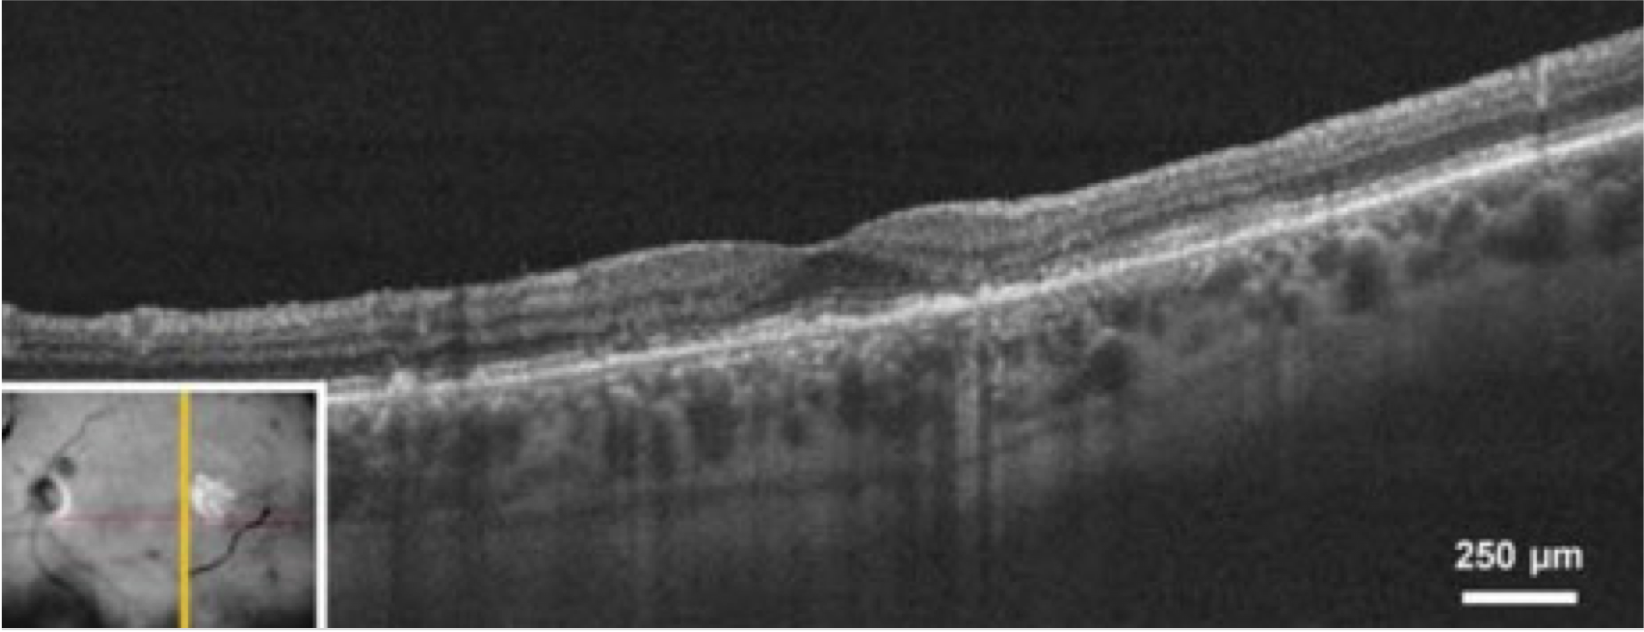

Optische Kohärenztomographie (OCT)

Die OCT ist ein wichtiges bildgebendes Verfahren für die Diagnose und Überwachung der AMD. Dabei werden Querschnittsbilder der Netzhaut aufgenommen, die eine umfassende Beurteilung des Zustands der Netzhaut ermöglichen. Die OCT kann die Netzhautdicke messen sowie Drusen und die choroidale Neovaskularisation (CNV) erkennen, die typische Merkmale der AMD sind.8,9